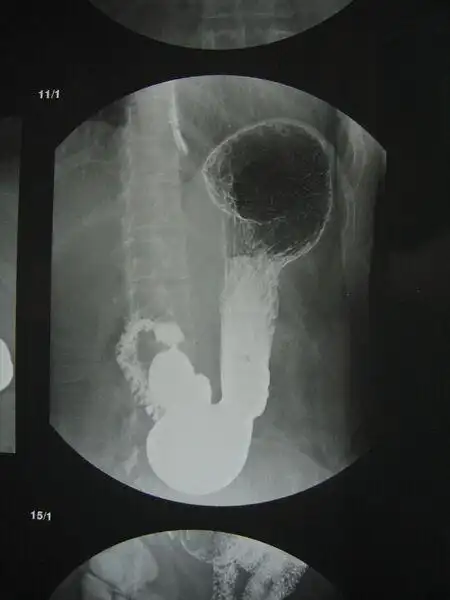

有没有小伙伴能帮忙看看片子,医生惜字如金,到现在我也不知道我的胃病

5 分钟读懂消化道造影片(胃篇)

胃下垂的无创治疗

"胃"君你越界了